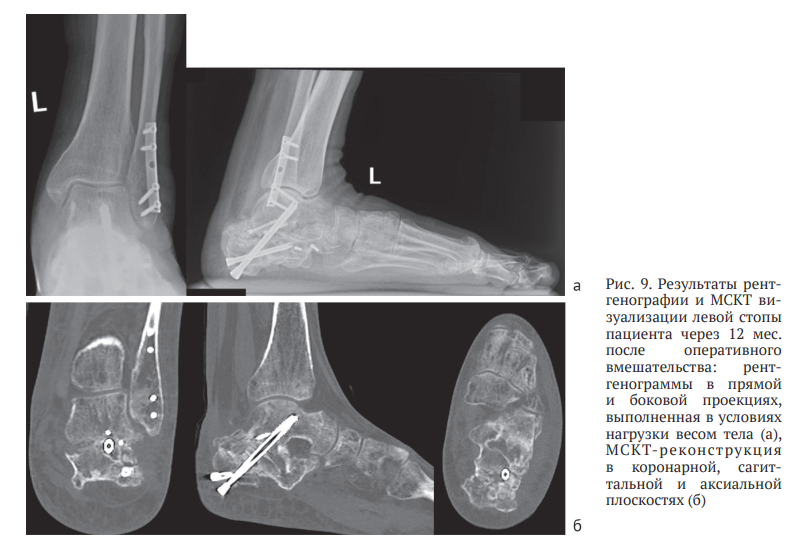

В течение месяца осевая нагрузка на конечность была полностью восстановлена, что позволило пациенту вернуться к трудовой деятельности. Динамическое наблюдение за пациентом продолжали, окончательный результат лечения оценен через 12 месяцев после операции. На контрольном осмотре отмечено сохранение достигнутой коррекции заднего отдела левой стопы, отсутствие латерального пяточно-малоберцового импиджмента, восстановление угла отклонения таранной кости, угла наклона пяточной кости, угла Мири, лодыжечного роста и ширины пяточной кости (рис. 9, а). Результаты МСКТ демонстрировали консолидированный артифициальный перелом левой пяточной кости с формированием подтаранного костного блока в условиях фиксации винтами, а также консолидированный перелом малоберцовой кости в условиях фиксации блокируемой пластиной (рис. 9, б).